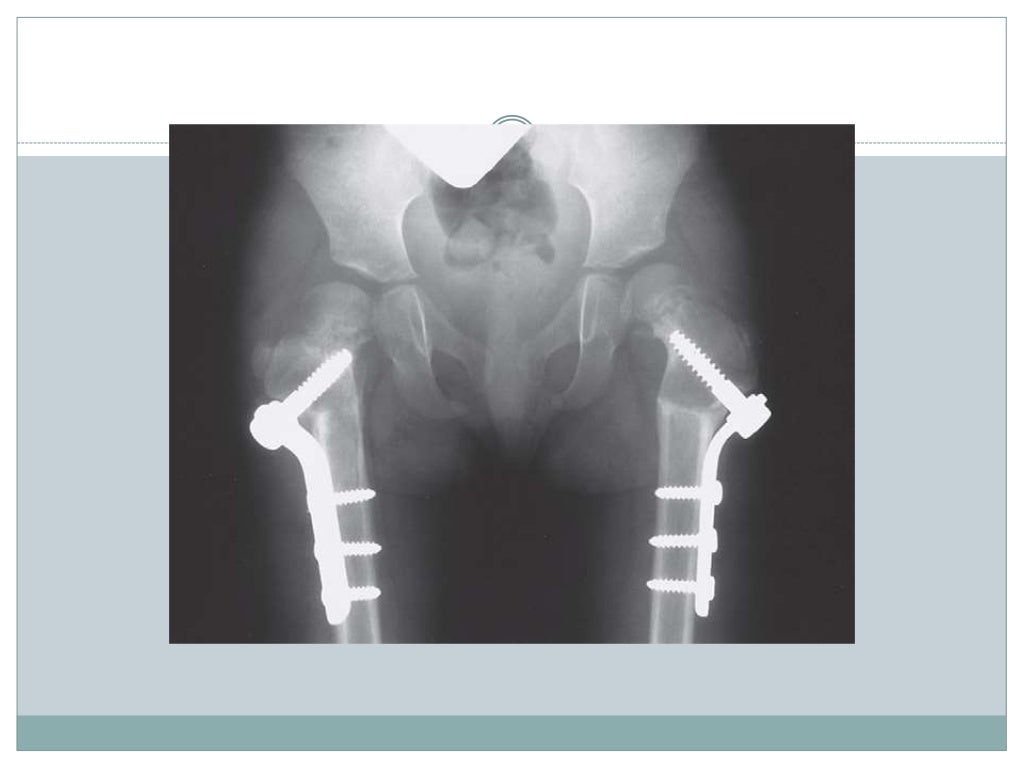

La definizione riguarda tutte quelle deformazioni dove l'angolo tra la testa del collo del femore e dell'asse del corpo risulti diminuito, o comunque risulti (parlando del collo del femore) eccessivamente orizzontale.

Il trattamento è soltanto chirurgico.